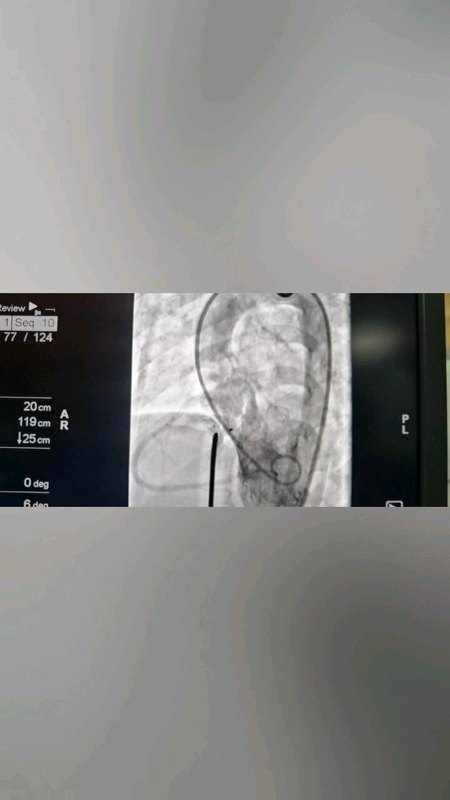

室間隔缺損是兒童最常見的先天性心臟病,近年來,隨著兒童先心病介入技術(shù)的不斷提高,絕大多數(shù)膜周部及肌部室缺都可以通過介入治療得到痊愈,一些位置異常的先心病也開始有了介入的機(jī)會。8歲的“萌萌”(化名)就是一位“嵴內(nèi)型”小室缺的患兒。來我院前家屬已經(jīng)咨詢了多家醫(yī)院,如果選擇開胸手術(shù),由于缺損小,不易尋找缺口,手術(shù)難度增加,并且創(chuàng)傷大,身體留下手術(shù)疤痕,心理也將受到影響,如果長期隨訪影響身心健康、學(xué)習(xí)和生活。為此“萌萌”家人來到了我的兒童心血管門診面診??紤]到“萌萌”為嵴內(nèi)型小室缺,并多次跟心臟超聲團(tuán)隊(duì)商討后,我們團(tuán)隊(duì)決定給“萌萌”進(jìn)行嵴內(nèi)型室缺封堵治療。術(shù)中造影發(fā)現(xiàn),“萌萌”的室缺分流口2.1mm,距離主動脈瓣很近,應(yīng)用常規(guī)室缺封堵器可能會造成明顯的主動脈瓣反流。根據(jù)造影結(jié)果,醫(yī)生跟家屬再次溝通后,決定應(yīng)用二代動脈導(dǎo)管未閉封堵器(ADO-Ⅱ)進(jìn)行封堵,此封堵器質(zhì)地更加柔軟,延展性強(qiáng),在封堵室缺的同時可最大限度的降低對主動脈瓣的損傷,術(shù)后心律失常的風(fēng)險也會減少。短短1個多小時,“萌萌”的室缺成功封堵,主動脈瓣沒有任何影響,“萌萌”的室缺治愈,術(shù)后4天出院,幾乎無手術(shù)疤痕。隨著介入治療技術(shù)的提高和介入器材的豐富,一些特殊類型的先心病也可以通過介入治療獲得痊愈:包括嵴內(nèi)型室缺、細(xì)小導(dǎo)管型及嬰幼兒動脈導(dǎo)管未閉、冠狀動脈瘺、肺隔離癥等。介入手術(shù)具有眾多優(yōu)點(diǎn):手術(shù)時間短、恢復(fù)快、創(chuàng)傷低等,現(xiàn)在可降解封堵器也將面世,未來將成為兒童先天性心臟病或者某些肺血管疾病的治療首選,更好的呵護(hù)兒童健康成長。劉麗萍副主任醫(yī)師門診:湖南省人民醫(yī)院(天心閣院區(qū)),小兒心血管門診,每周五上午。綠色熱線:0731-83929461;